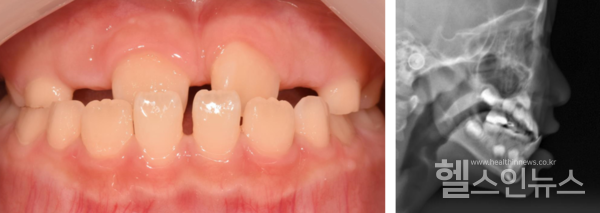

즉각적인 치료가 필요할 때도 있다. 대표적으로, 윗턱보다 아래턱이 앞으로 나와 윗니와 아랫니가 거꾸로 물리게 되는 ‘반대교합’의 경우다. 반대교합은 만 7~8세 경 영구치가 맹출하는 시기에 주로 치료하지만, 정도가 심한 경우 유치열기(생후 6개월로부터 최초 영구치가 나타나기 직전까지의 기간)에서도 치료한다.

반대교합과는 반대로 아래턱이 윗턱에 비해 성장하지 못해 소위 ‘무턱’이라 불리는 ‘하악후퇴증’도 있다. 이 경우, 윗니가 아랫니를 깊게 덮는 ‘과개교합’이나 턱관절 장애를 동반하기도 한다. 하악후퇴증의 치료는 윗턱 성장을 억제하고 아래턱 성장을 촉진하는 악정형치료를 진행한다.